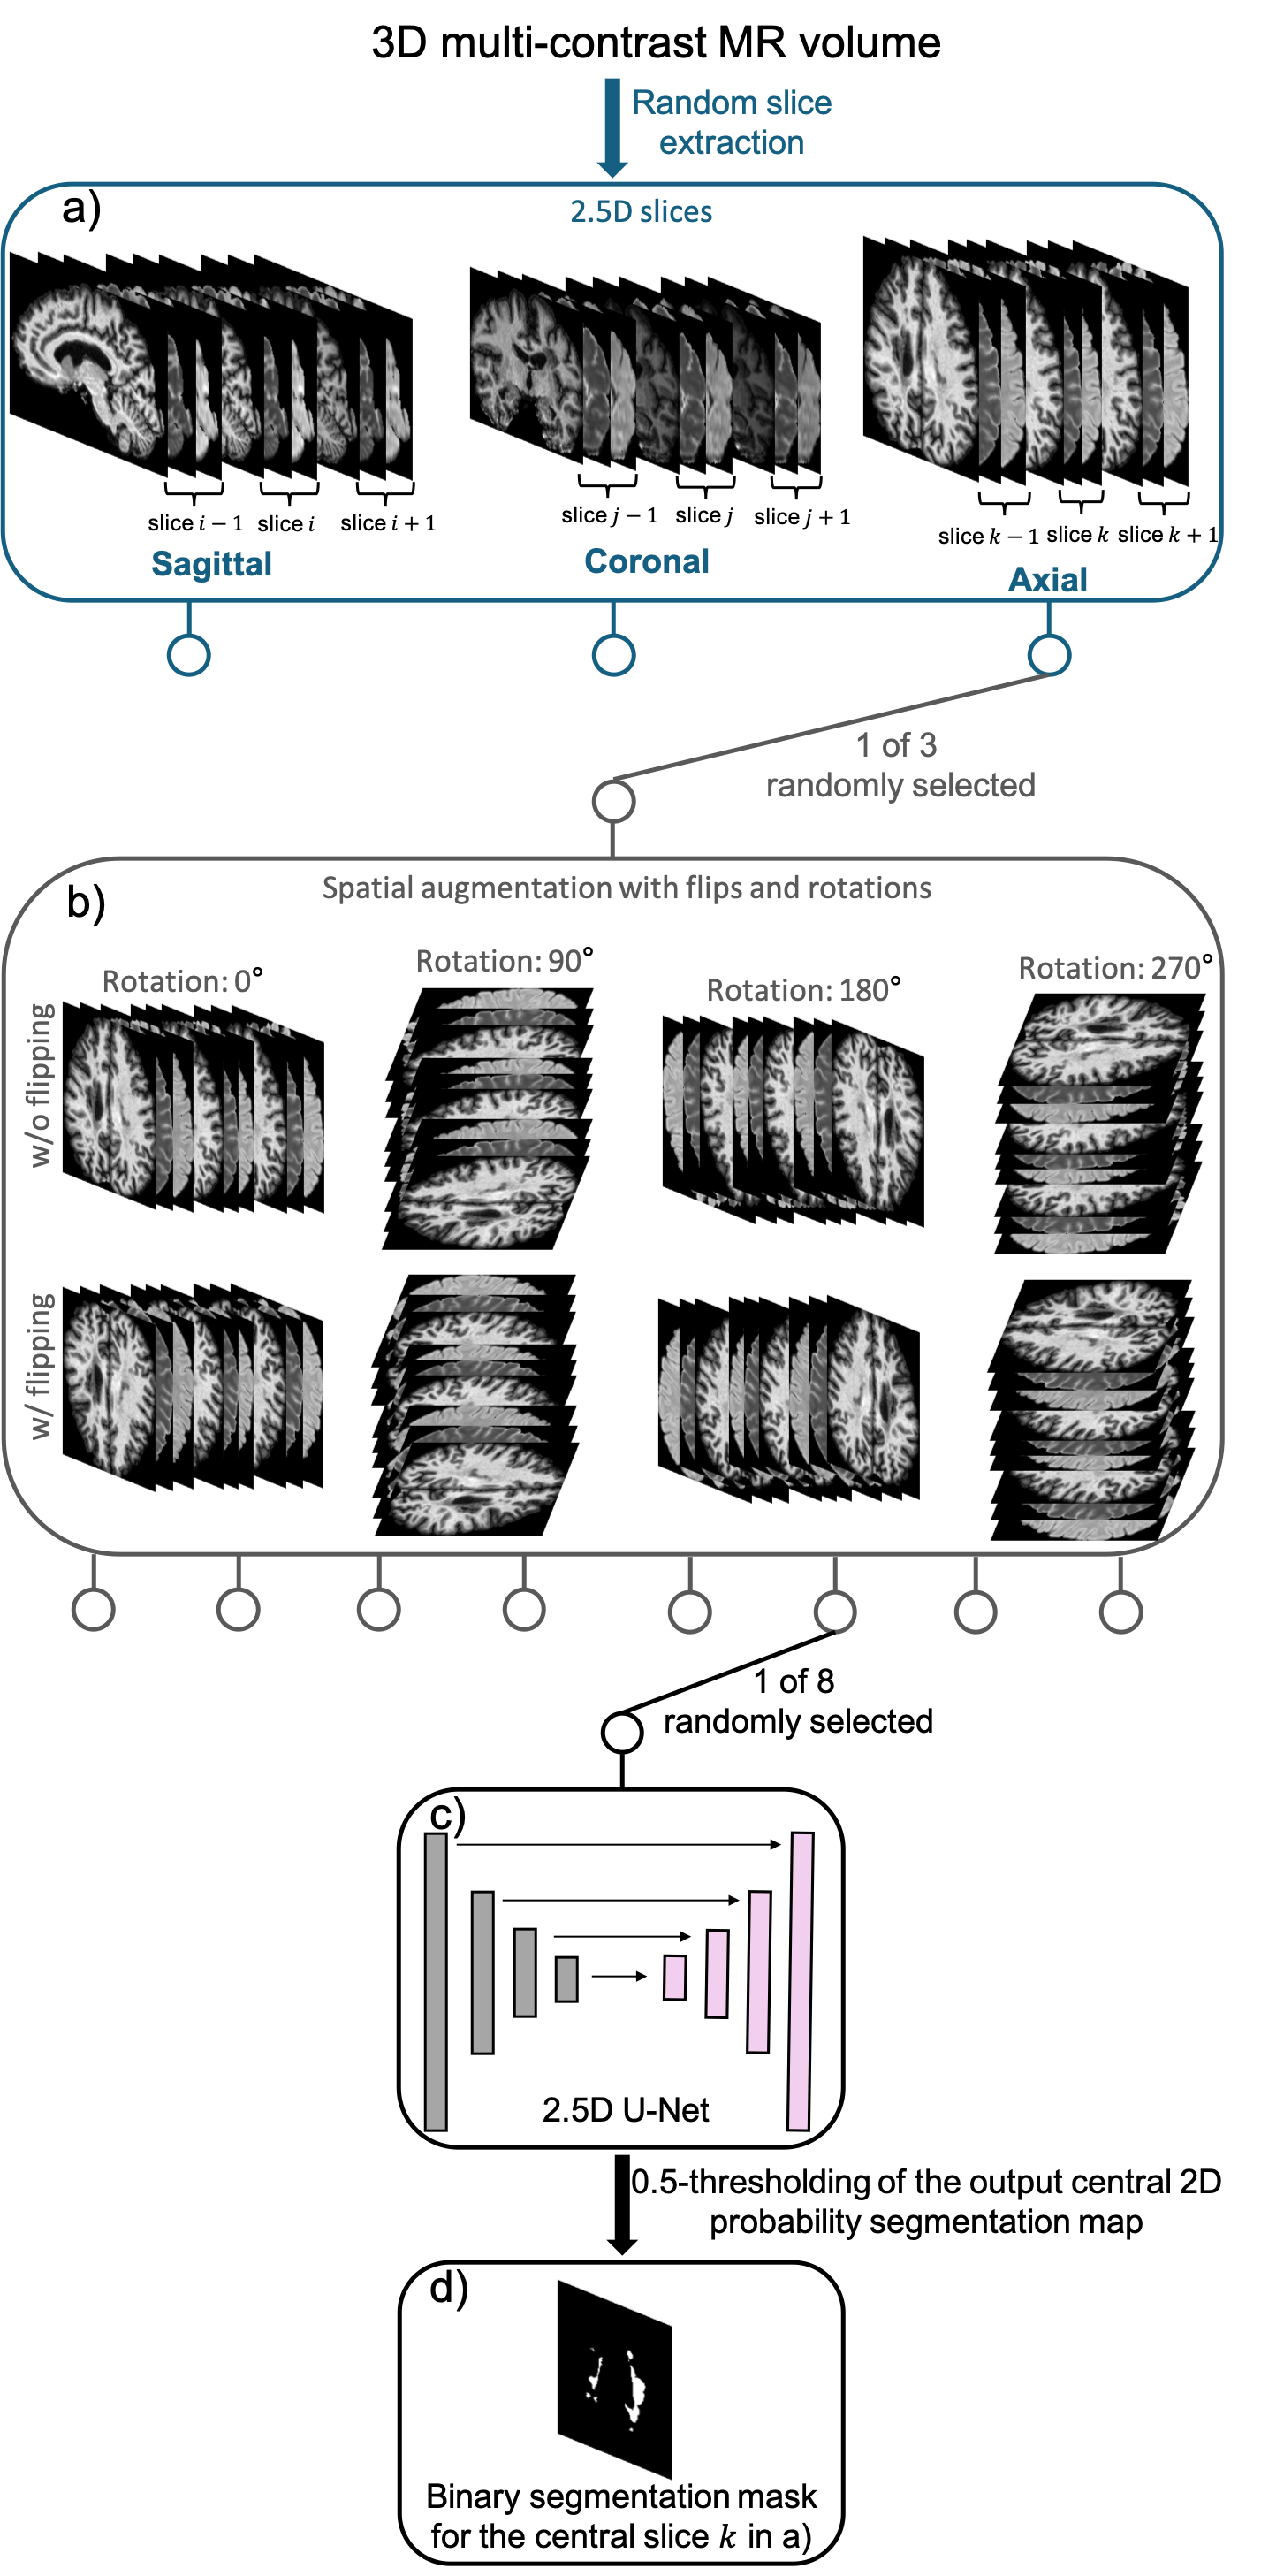

In UNISELF, a single U-Net is trained to slice-wise process multicontrast 3D MRI volumes with multi-orientation augmentation. Figure 1 presents an overview of the multi-orientation data augmentation process applied during training. In Fig. 1a, three adjacent 2D slices of multicontrast MRI, concatenated along the channel dimension with zero-padding at the boundaries (referred to as 2.5D input [76]), are extracted from a random selection of the three cardinal planes: axial, sagittal, or coronal. In Fig. 1b, a randomly selected augmentation from 8 possible augmentations, including flips (vertical and horizontal) and rotations (, , , and ), is applied to the extracted 2.5D input. These augmentations alter the spatial configuration of the 2.5D input without changing its intensity values, preserving the original image information while enhancing the diversity of inputs encountered by the network during training. In Fig. 1c, the augmented 2.5D input is fed into the network to generate the probabilistic output map of the central 2D slice. In Fig. 1d, a binary segmentation mask is obtained from the augmented 2.5D input by applying a threshold of 0.5 to the output probabilistic map, classifying pixels with values above 0.5 as lesion and those below as non-lesion areas. The ground truth lesion mask of the central slice undergoes the same augmentation process as in Figs. 1a and b and is used in the loss function for backpropagation.

Confidence Map in Test Time

At test time, a confidence map is generated through comprehensive multi-orientation processing and aggregation of the same multicontrast 3D volume using the trained segmentation model. Specifically, the eight spatial augmentations shown in Fig. 1b are applied to each of the three cardinal plane 3D volumes, resulting in augmented multicontrast 3D volumes. For any augmented input volume with index , the trained network processes the volume in a 2.5D fashion, where 2D binary segmentation masks are generated slice-by-slice and subsequently stacked to form a 3D binary mask corresponding to the augmented input volume. The resulting 3D binary mask is then flipped and rotated back into the original space, denoted as , where represents the spatial coordinate of a 3D voxel in the original space. A confidence map with integer values between and is then generated by adding 3D binary masks in the original space:

| (1) |

This confidence map indicates the number of times that the network, trained with all cardinal planes, rotations, and flips, predicts a voxel as part of a lesion. Figure 2a shows an example as a heatmap ranging between integer values of 0 and 24. For example, means that the model consistently predicts the voxel at as belonging to a lesion under all spatial augmentations. We use to derive the final lesion segmentation mask through a two-step process of lesion detection and connected lesion growth, as detailed in the next section.